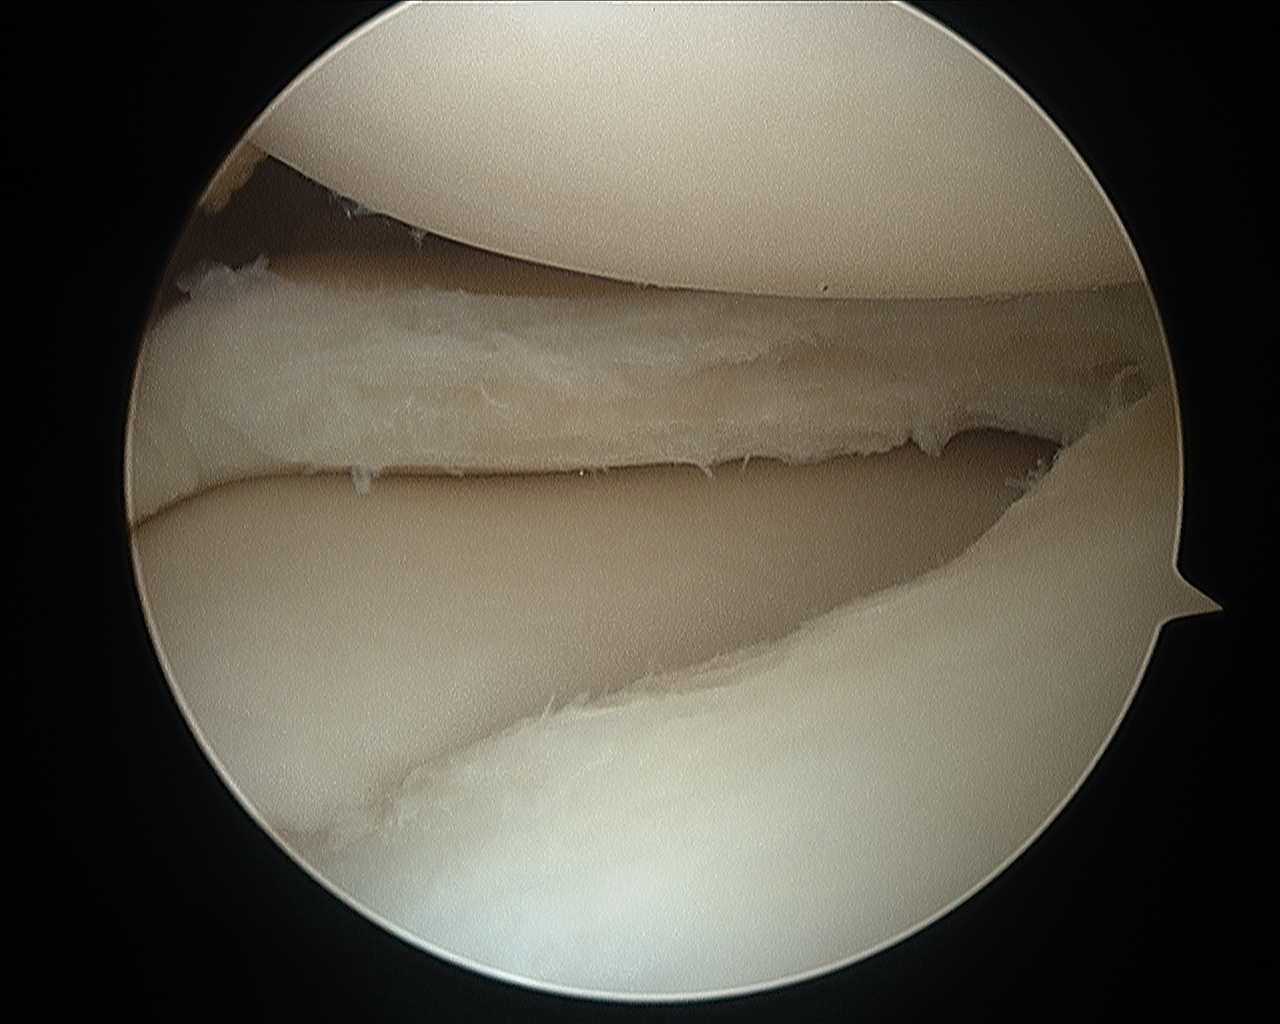

δισκοειδής μηνισκος πριν την χειρουργική παρέμβαση                      δισκοειδής μηνισκος μετά την χειρουργική παρέμβαση

δισκοειδής μηνίσκος πριν την χειρουργική παρέμβαση                  δισκοειδής μηνίσκος μετά την χειρουργική παρέμβαση